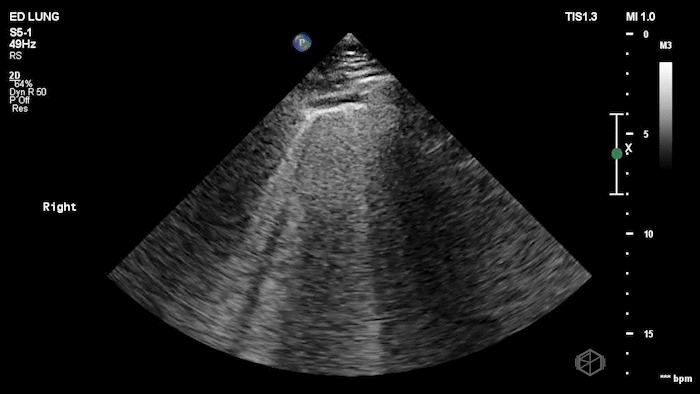

19 - What is the ultrasound finding, and what are two differentials?

Abolished lung sliding with focal B-lines; pneumonia, malignancy.